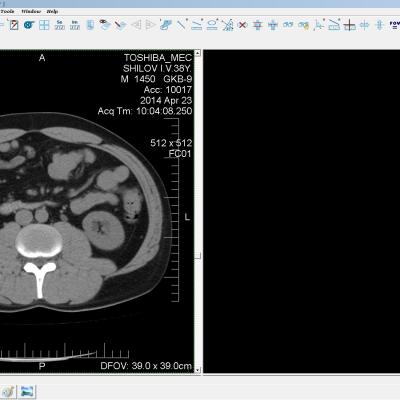

Здравствуйте. У меня киста левой почки. Из заключения: левая почка увеличена, деформирована за счёт наличия в среднем сегменте округлого жидкостного +6, +15 HU образования 66х53 мм, деформирует, поддавливает чаше-лоханочную систему. Сосудистые ножки структурные. В урологии мне сперва предложили лапароскопию, когда я лёг на операцию - изменили на полостную в связи со сложностью. Потом сказали что шансов вырезать кисту без почки практически нет. Даже если кисту удалить чудесным способом, то почка всё равно сложится и не будет работать. В итоге операцию отменили. Скажите, пожалуйста, есть ли современный метод удалить кисту и сохранить почку в моём случае? Томография почки в приложениях. Заранее благодарю.

Эту кисту можно просто пропунктировать, аспирировать и склерозировать - под местной анестезией. Ничего сверхестетственного не определяется по данным КТ. Можете написать мне на почту. aristova-tatyana@mail.ru